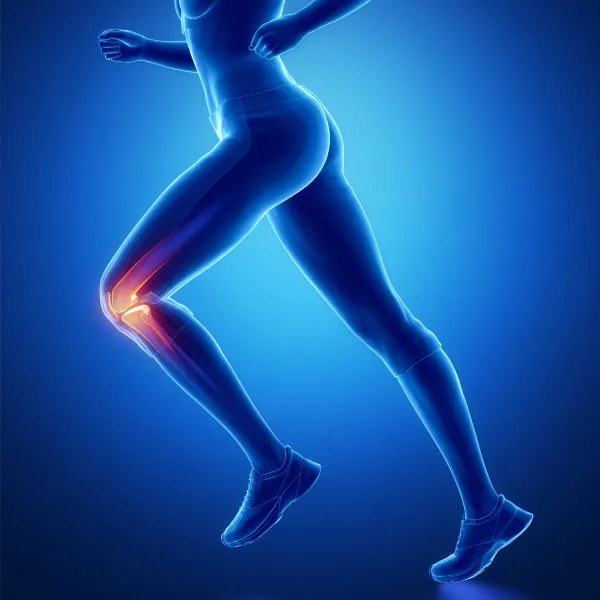

Один из самых нагружаемых суставов в организме. Диагностируем и лечим травмы связок, менисков, хрящевой ткани, переломы, а также болевые синдромы и воспалительные процессы.